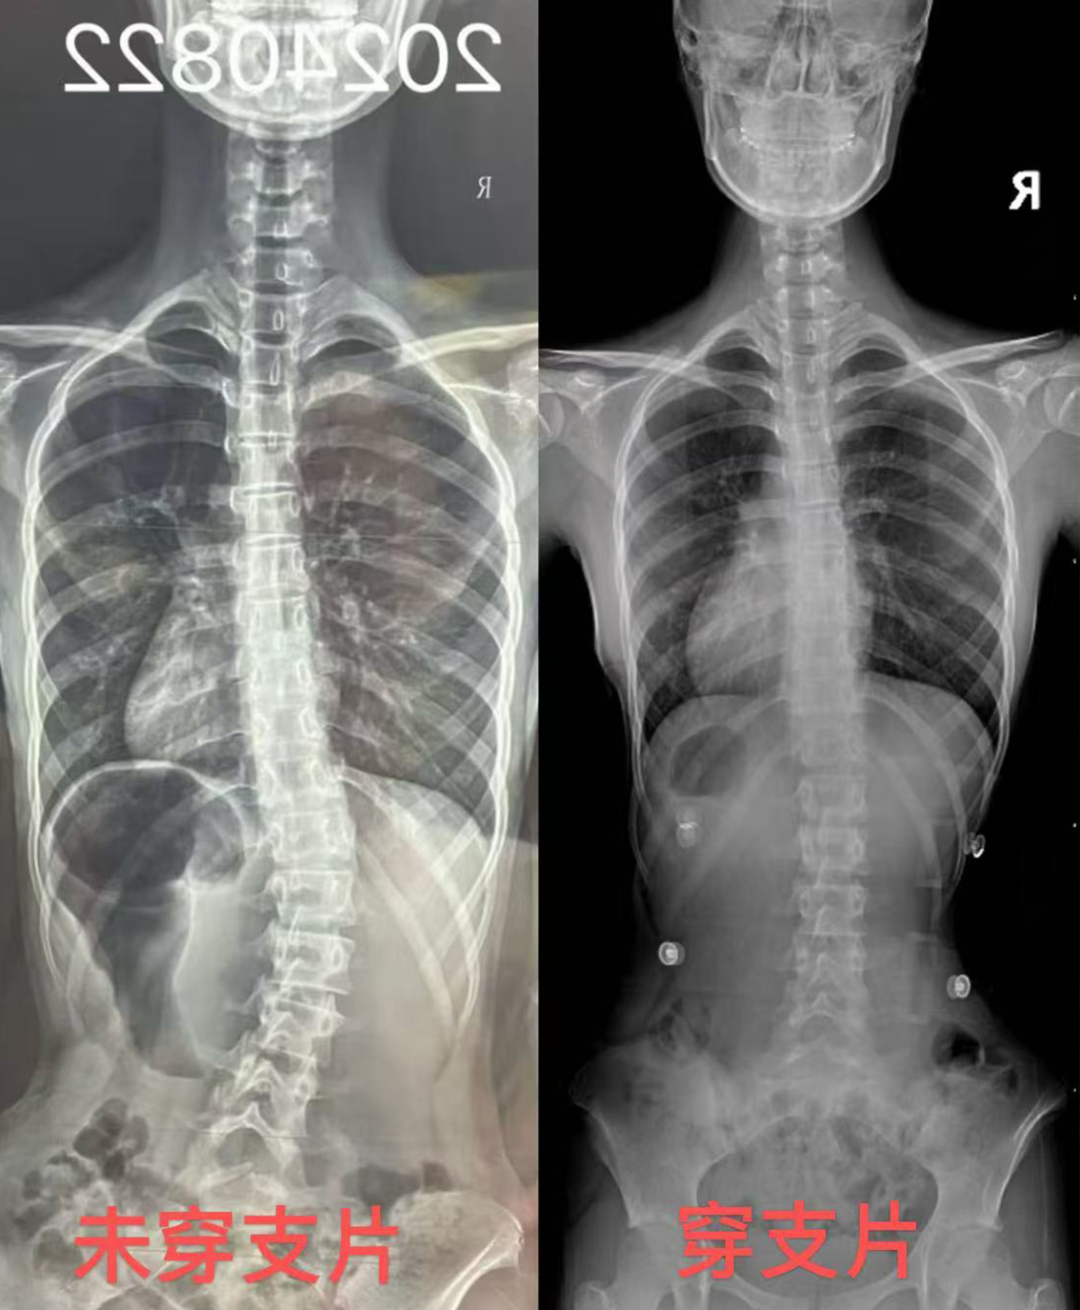

专业诊断:专家解读全脊柱X光片 + 步态生物力学分析